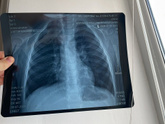

Сняли рентген легких сыну , чтобы проверить .

Я случайно заметила что печень огромная ??? эта так должно быть ? Или мне надо срочно на узи ???

Сын кашляет ужасно , тема 38-39 , понос . И эта сегодня заметила ???